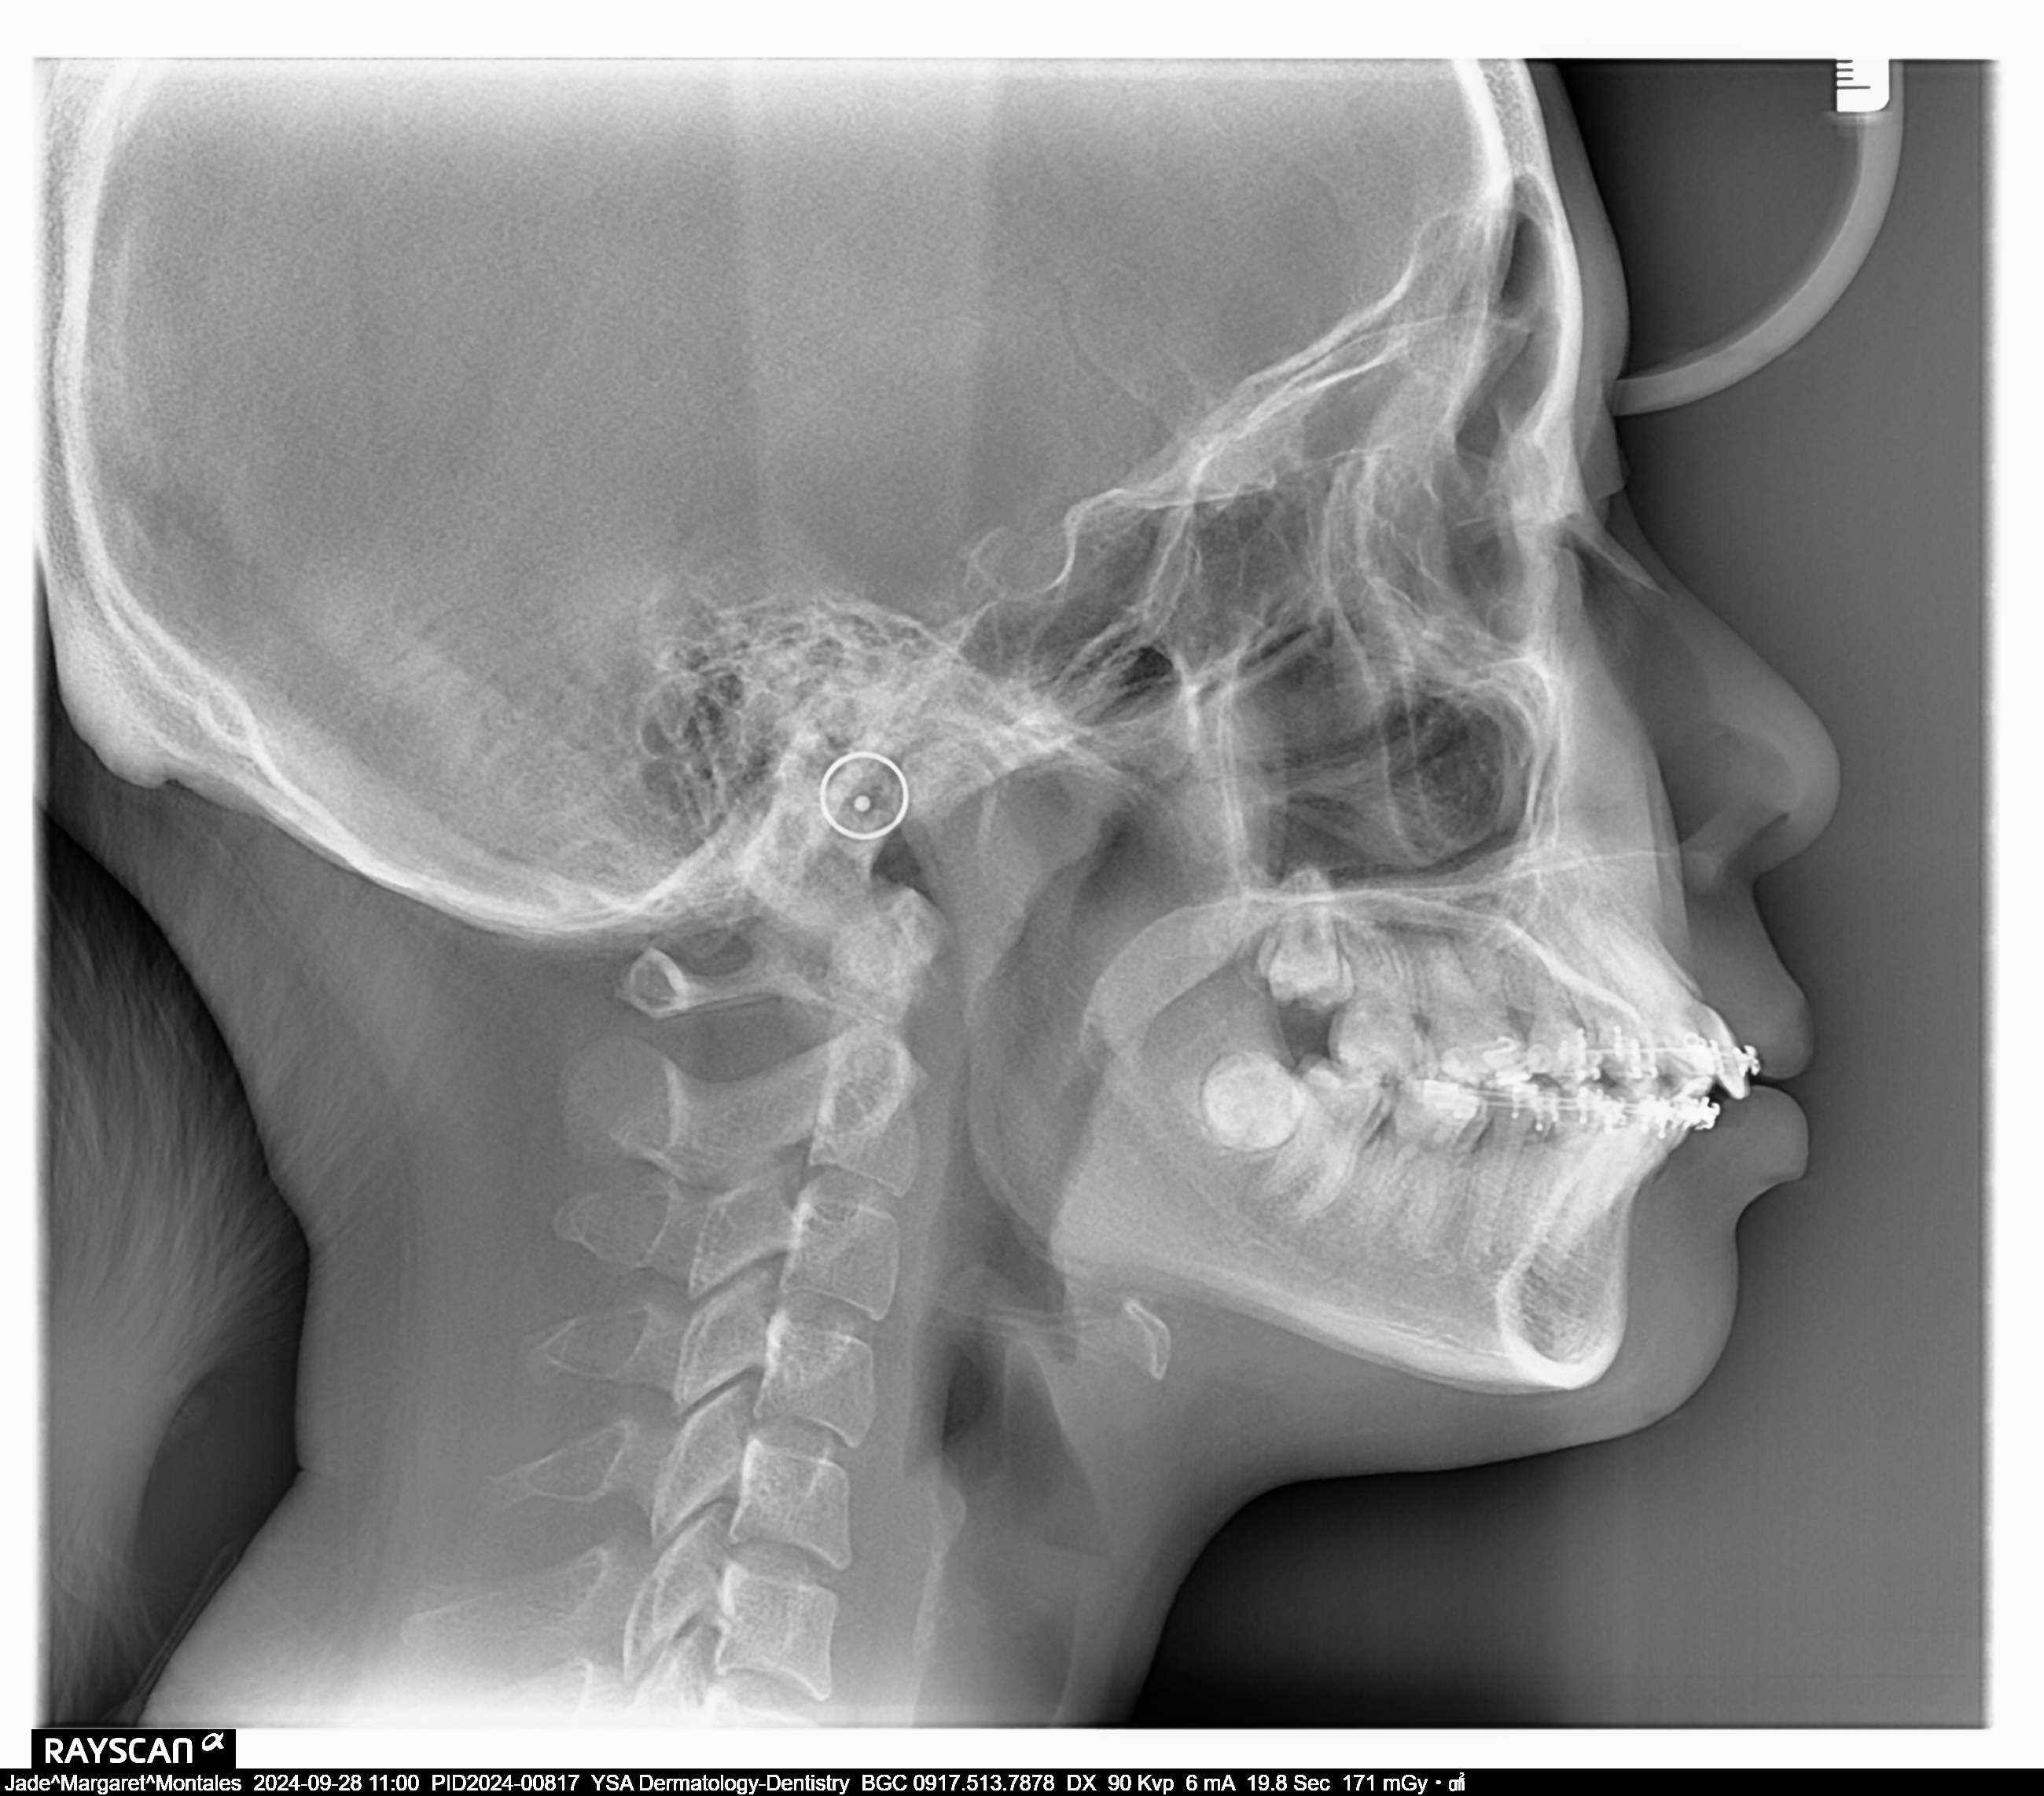

- Last Name

- Montales

- First Name

- Jade Margaret

- Birthdate

- March 31, 2003

- Age

- 21

- Phase II to Phase III- 50 ,000 less 40% 20,000 DP 5,000 reposition canine 13/23 15,000 balance for 6-8 months lost buccal tube 1,000 06/21/24 class II elastic rabbit 3.5 oz loop to 36/46 18 SS U/L U w/loop new #46 Op heavy plaque lower BOP 70% 08/01/24 RW #21 M class II elastic rabbit 3.5 0z 09/28/24 class II elastic rabbit 5oz. Adj 10/28/24 16x16 SS U class II elastic rabbit 30z 11/29/24 same wire extrude 13 -15 01/31/25 16x16 SS L Adj 02/28/25 Adj #12/22 kobayashi wire box elastic rabbit 3 oz 03/28/25 class II rabbit 5oz closing bite-chipmunk L to R reattached #15 05/27/25 same wire 34-4 (L&R) chipmunk class II elastic- rabbit 5 oz 07/01/25 Adj 09/04/25 Adj same wire U 16x22 L elastic penguin

- file_0001_4_1.jpg